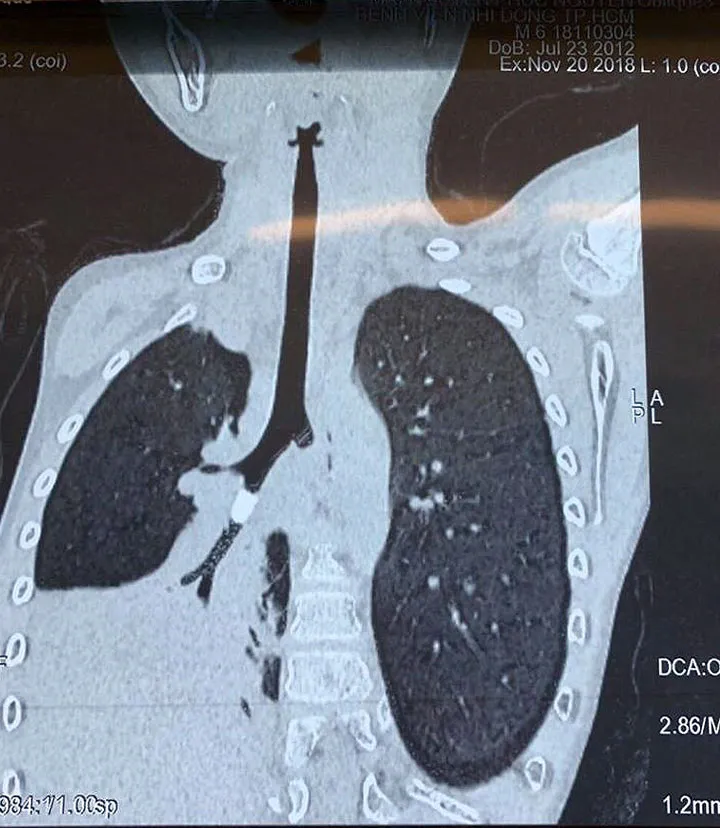

Sau khi thăm khám, các bác sĩ đã nhận thấy rõ hội chứng xâm nhập và tắc nghẽn tại phổi phải, hình ảnh chụp X-quang ngực tức thì không cho thấy rõ có dị vật lạ. Tuy nhiên, sau khi hội chẩn, TS.BS Trịnh Hồng Nhiên, trưởng khoa Hô Hấp Bệnh viện Nhi Đồng Thành Phố cho rằng, có vùng bẫy không khí trong phim chụp x-quang phổi, kết hợp với phim CT scan ngực thấy có sự hiện diện của một vật thể lạ trong phế quản, dạng hình trụ, bít lòng hoàn toàn nhánh phế quản S9 dẫn tới việc không khí không thể đi qua hoàn toàn vật thể, gây tắc và xẹp toàn bộ nửa phổi phải.